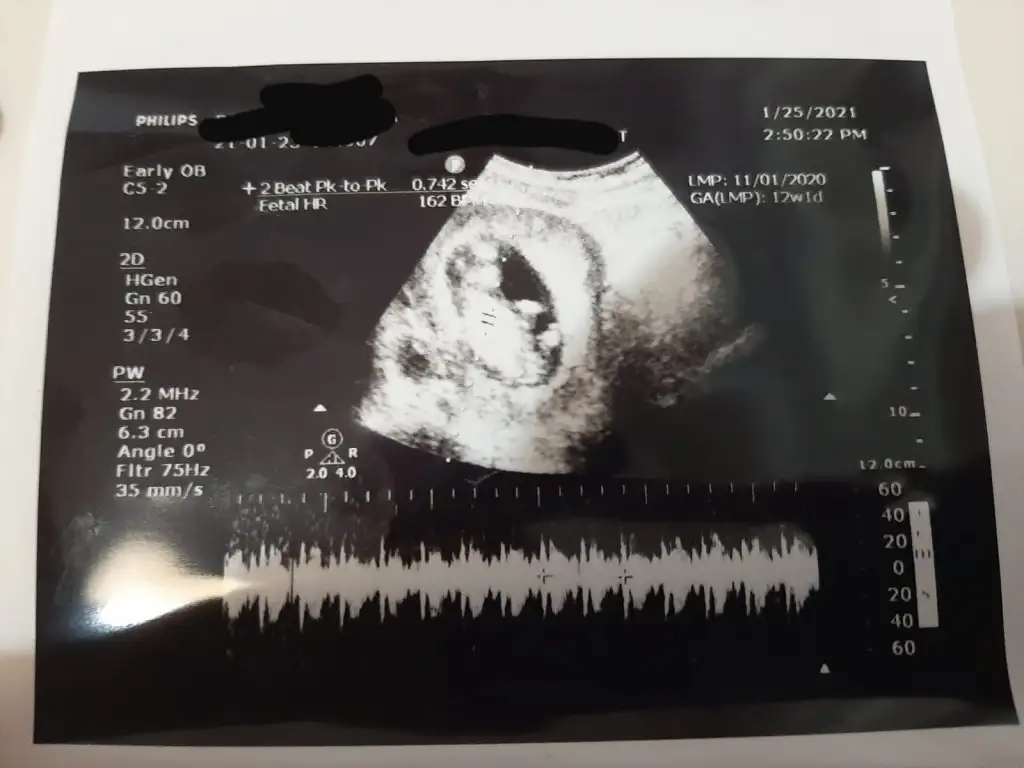

Emin olamadim kız gibi sanki başka USG varsa paylaşınMerhabaIkra meyra bana da bakmanız mümkün mü acaba hem 11+3 hem 12+1 haftalık resimleri attım

11 hafta göre erkek görünüyorIkra meyra başka yerde size sordum ama anketinize dahil olayım burda da sorayım sırasıyla atıyorum ilk resim11 haftalık ve son iki resim14 haftalık